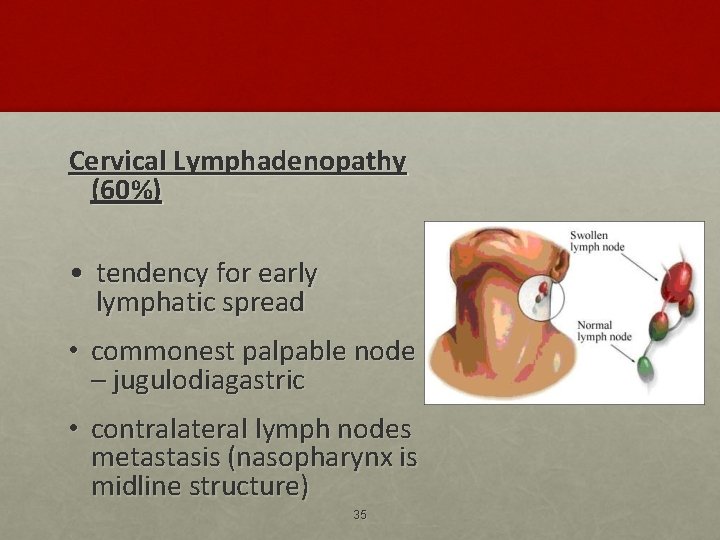

Cervical Lymphadenopathy (60%) • tendency for early lymphatic spread • commonest palpable node – jugulodiagastric • contralateral lymph nodes metastasis (nasopharynx is midline structure) 35